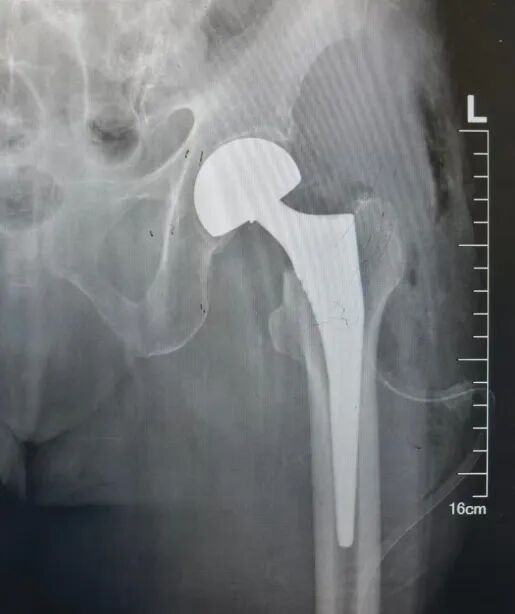

刘大诚主刀,杨效宁主任全程指导,主治医师孙一公、宋子鉴担任助手。刘大诚娴熟地将患者已经骨折的股骨头取下,然后精准选取合适的股骨头假体为患者安装。安装完成后,他仔细检查髋关节各项活动,确认关节活动不受影响、稳定性佳、匹配度良好不脱位。

器械护士贾惠清、巡回护士刘雯丽紧密配合,麻醉医师全程保驾护航。在团队的密切协作下,这台通常需要1-2小时的四级手术,仅用40分钟就顺利完成。